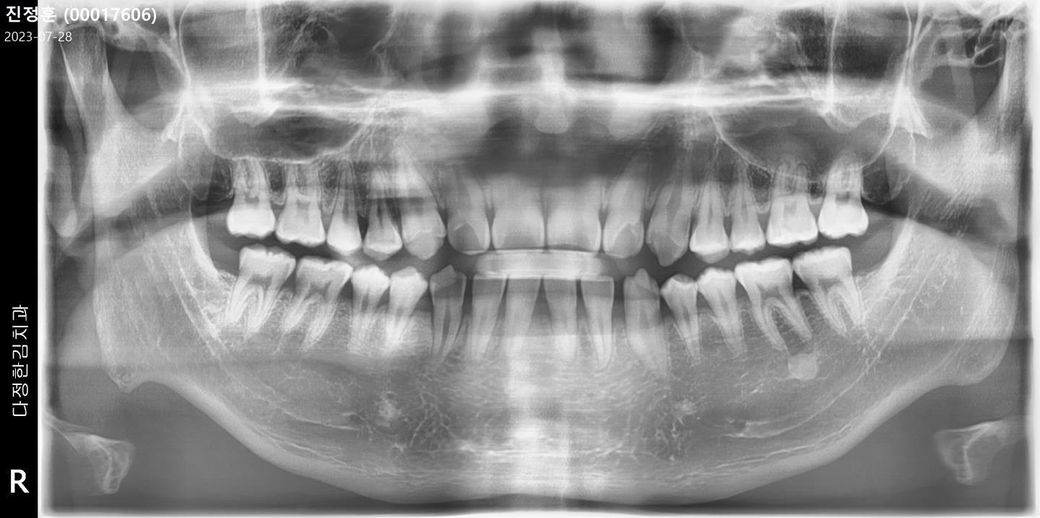

왼쪽 상단 2번쨰 어금니입니다

첨부사진은 지난주 엑스레이 사진입니다